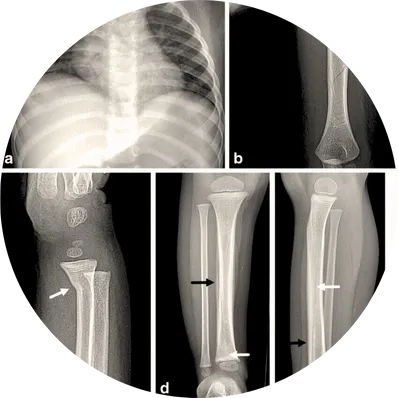

Implant removal surgery is a procedure to take out orthopedic implants (such as plates, screws, rods, or pins) that were used to stabilize bones after a fracture or corrective surgery. While implants are usually designed to stay permanently, sometimes they need to be removed due to complications or discomfort.

Causes (Leading to Joint Damage)